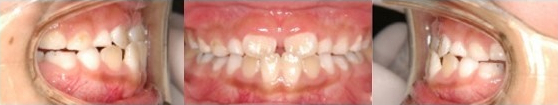

Pre-Ortho type 1. 과개교합 전용

8세여아, 프리올소 착용 4개월 후

첫 번째는 과개교합 전용 타입인데요.

앞니가 깊게 물린 과개교합에 치열이 심하게

틀어져있지만 이를 착용함으로써

올바른 성장을 유도하고, 2차교정에 들어갈 때

유리하게 적용됩니다.